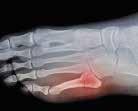

Footballers tend to have many metatarsal injuries, usually fractures such as Jones and/or March fractures. The ‘Jones’ fracture is a transverse fracture of the proximal metadiaphyseal junction of the fifth metatarsal bone involving the 4th-5th metatarsal articulation. The fracture is believed to occur because of significant adduction force to the forefoot with the ankle in plantar flexion (Theodorou et al, 2003).

The ‘March’ fracture was derived in 1855 because of the effects of Prussian soldiers marching. The marching often caused stress fractures affecting one or more of the metatarsals of the foot. This occurred because of overuse and repetitive actions of the feet (Van Demark and McCarthy, 1946)